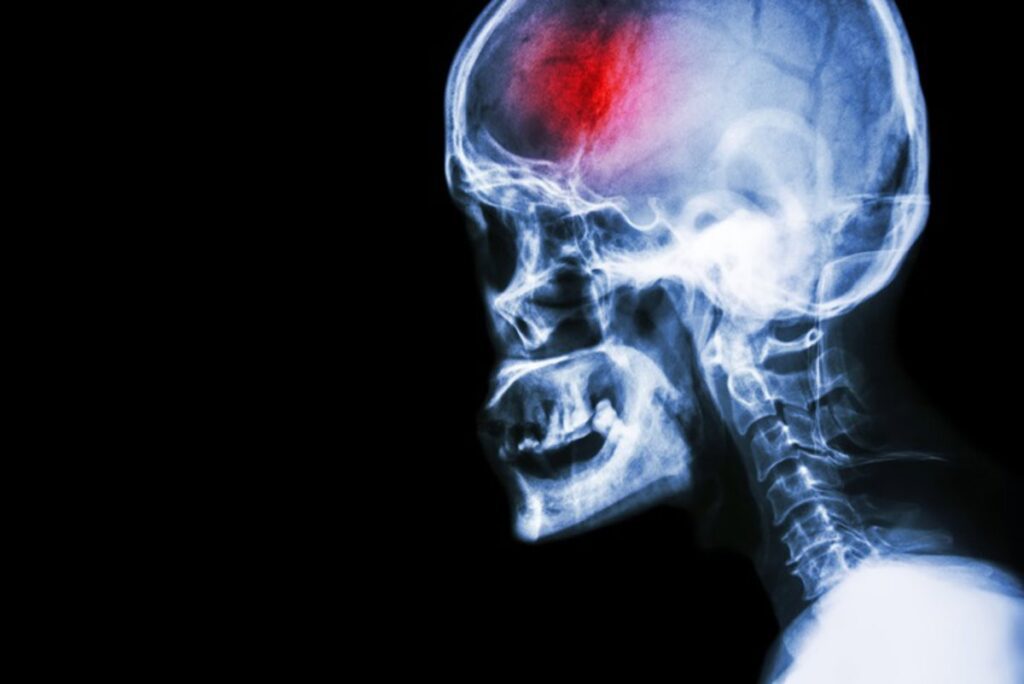

El momento del día en que se produce el ictus condiciona su gravedad y la recuperación del paciente, según un estudio liderado por investigadores del Centro Nacional de Investigaciones Cardiovasculares (CNIC), que revela hallazgos sobre la regulación que ejerce el reloj biológico interno en los neutrófilos, células inmunes que pueden agravar la lesión isquémica infiltrándose en el cerebro.

El ictus isquémico es una de las principales causas de muerte y discapacidad en el mundo. A pesar de los avances en el tratamiento agudo, la evolución de los pacientes sigue siendo muy variable, lo que indica la existencia de mecanismos biológicos aún poco comprendidos. Este trabajo, publicado en Circulation Research, identifica la regulación circadiana de la respuesta inmune como uno de ellos.